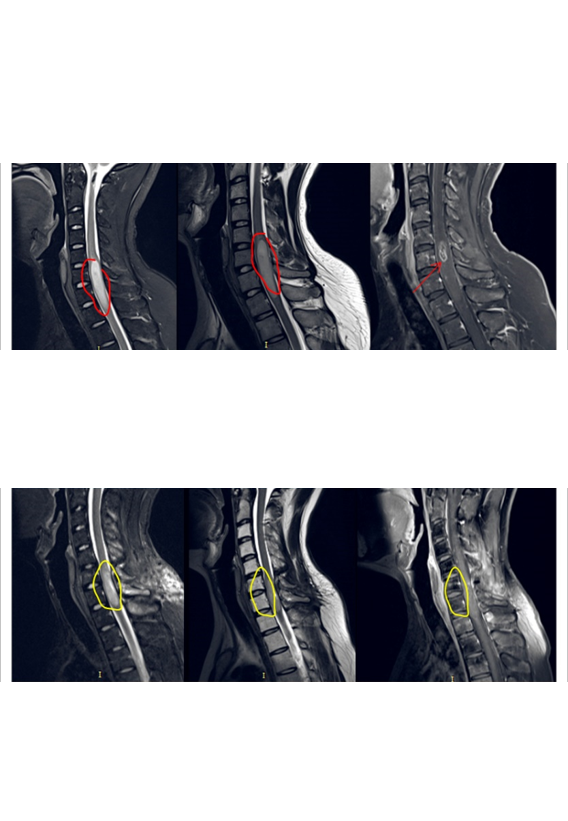

“腫瘤位置太不同、手術(shù)困難太大,殘疾的可能性很大……”一位22歲髓內(nèi)腫瘤占位的男士,頸后部疼痛,手臂麻木半年。咨詢(xún)了國(guó)內(nèi)一些大醫(yī)院,醫(yī)生們都這樣告訴他。好在咨詢(xún)了很多國(guó)外治療辦法,得知INC國(guó)際神經(jīng)外科顧問(wèn)團(tuán)有位被國(guó)內(nèi)尊稱(chēng)為“巴教授”對(duì)脊髓髓內(nèi)、腦干等“手術(shù)禁區(qū)”內(nèi)的腫瘤切除較為擅長(zhǎng)。于是通過(guò)INC前往教授所在醫(yī)院德國(guó)INI接受治療,教授對(duì)其行髓內(nèi)占位切除術(shù)、頸5-6椎體成行術(shù),瘤體強(qiáng)化部分被完整切除。術(shù)后10天出院,精神狀態(tài)佳。